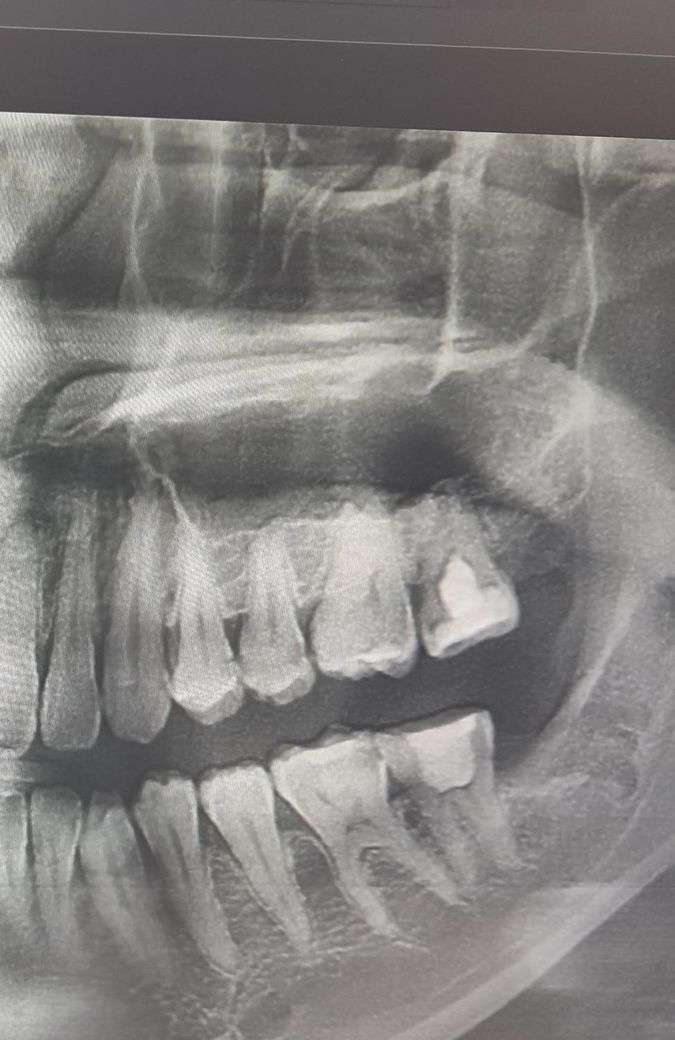

왼쪽 위의 어금니도 재신경치료를 받아야 할까요??

현재 왼쪽 아래 사랑니를 빼고 왼쪽 아래 어금니는 재신경치료 중에 있습니다.

다만 담당 주치의 분께서 왼쪽 위에 마지막 어금니도 재신경치료가 필요하다고 하는데 혹시 이쪽 치아도 치룐를 받아야 할까요??

신경치료가 뿌리끝에까지 되어있지는 않은 상태는 맞습니다. 하지만 특별한 증상이 없고 병소가 없다면 굳이 치료를 할 필요는 없을것으로 생각됩니다.

엄밀히 말하면 재신경치료 아닙니다. 지금 되어있는건 신경치료가 아니고 치수절단술로 부분적으로 신경치료를 해둔 겁니다. 증상이 생기면 완전 치수절제술 (완전 신경치료)를 해줍니다 증상 없두면 냅둡니다. 증상 없는데 건드릴 이유가 없습니다. 다만, 왼쪽 위 어금니도 적절한 차단과 밀폐를 위해 크라운은 씌워줄 필요가 있습니다.

일단은 불편한게 없다면 그냥 사용하시는게 좋지만 크라운 치료를 하지 않아서 크라운 치료를 다시 하시는게 좋을것같긴합니다.